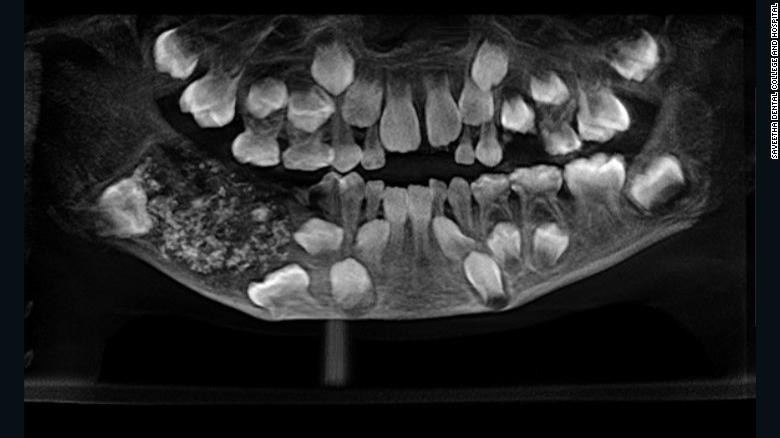

Khi các bác sĩ chụp x-quang khoang miệng, họ phát hiện một bọc sưng ở hàm dưới chứa đầy "răng bất thường", bác sĩ Prathiba Ramani, trưởng khoa Bệnh lý Răng miệng và Phẫu thuật miệng - hàm mặt tại Bệnh viện Saveetha, cho biết.

"Có tổng cộng 526 chiếc răng từ 0,1 mm đến 15 mm. Ngay cả mảnh nhỏ nhất cũng có mão, chân răng và lớp men cho thấy đó là một chiếc răng", bác sĩ Ramani nói.

Bác sĩ phát hiện khối u chứa hơn 500 chiếc răng trong miệng cậu bé 7 tuổi ảnh 1

Toàn bộ số răng được lấy khối u của bệnh nhi.